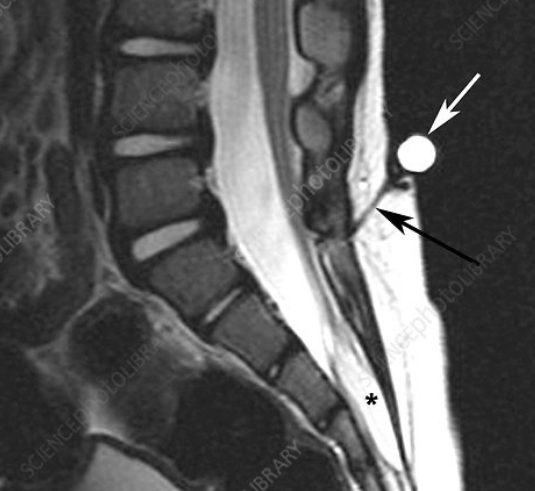

MRI Scan

Lipoma or Dermal Sinus Tract

Conus Medullaris Level and Filum Terminale Thickness (Tethered Cord)